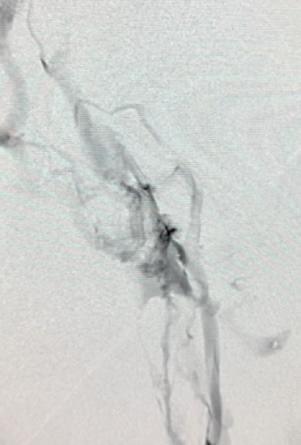

1. Pre-procedural venogram. 2. Venogram taken post-procedure 3. A representation of the clot removed. 4. The RevCore (top) and VenaCore (bottom) devices used

A man in his late 60s with a left iliac vein stent and revision two years prior was referred for consultation. The patient dis -

continued his anticoagulation two months before he was referred for consultation for severe left leg swelling. Duplex ultrasound confirmed a reoccluded left iliac venous stent. The decision was made to intervene with mechanical thrombectomy.

Procedural overview

Access was obtained in the superficial femoral vein and right internal jugular (IJ) vein under ultrasound guidance. A venogram demonstrated significant thrombus in the common femoral vein, profunda and extending into the external iliac vein. A .035” guidewire was inserted into the femoral vein and externalized through the access sheath. A ProtrieveTM sheath (Inari Medical) was inserted over the wire into the right IJ vein and advanced into the inferior vena cava. Next, the Triever20 catheter (Inari Medical) was inserted over the wire and directed to the profunda and common femoral vein. Aspiration with the Triever20 removed acute and sub-acute thrombus. Organized material could not be removed with aspiration. RevCore was then inserted over the wire into the occluded stent. Multiple clockwise and counterclockwise turns in conjunction with scrubbing the element within the stent resulted in successful clearance of nonacute thrombus. VenaCore was then introduced through the Protrieve sheath to clear the common femoral vein. Completion venogram demonstrated brisk cephalad flow. Total procedure time was 90 minutes.